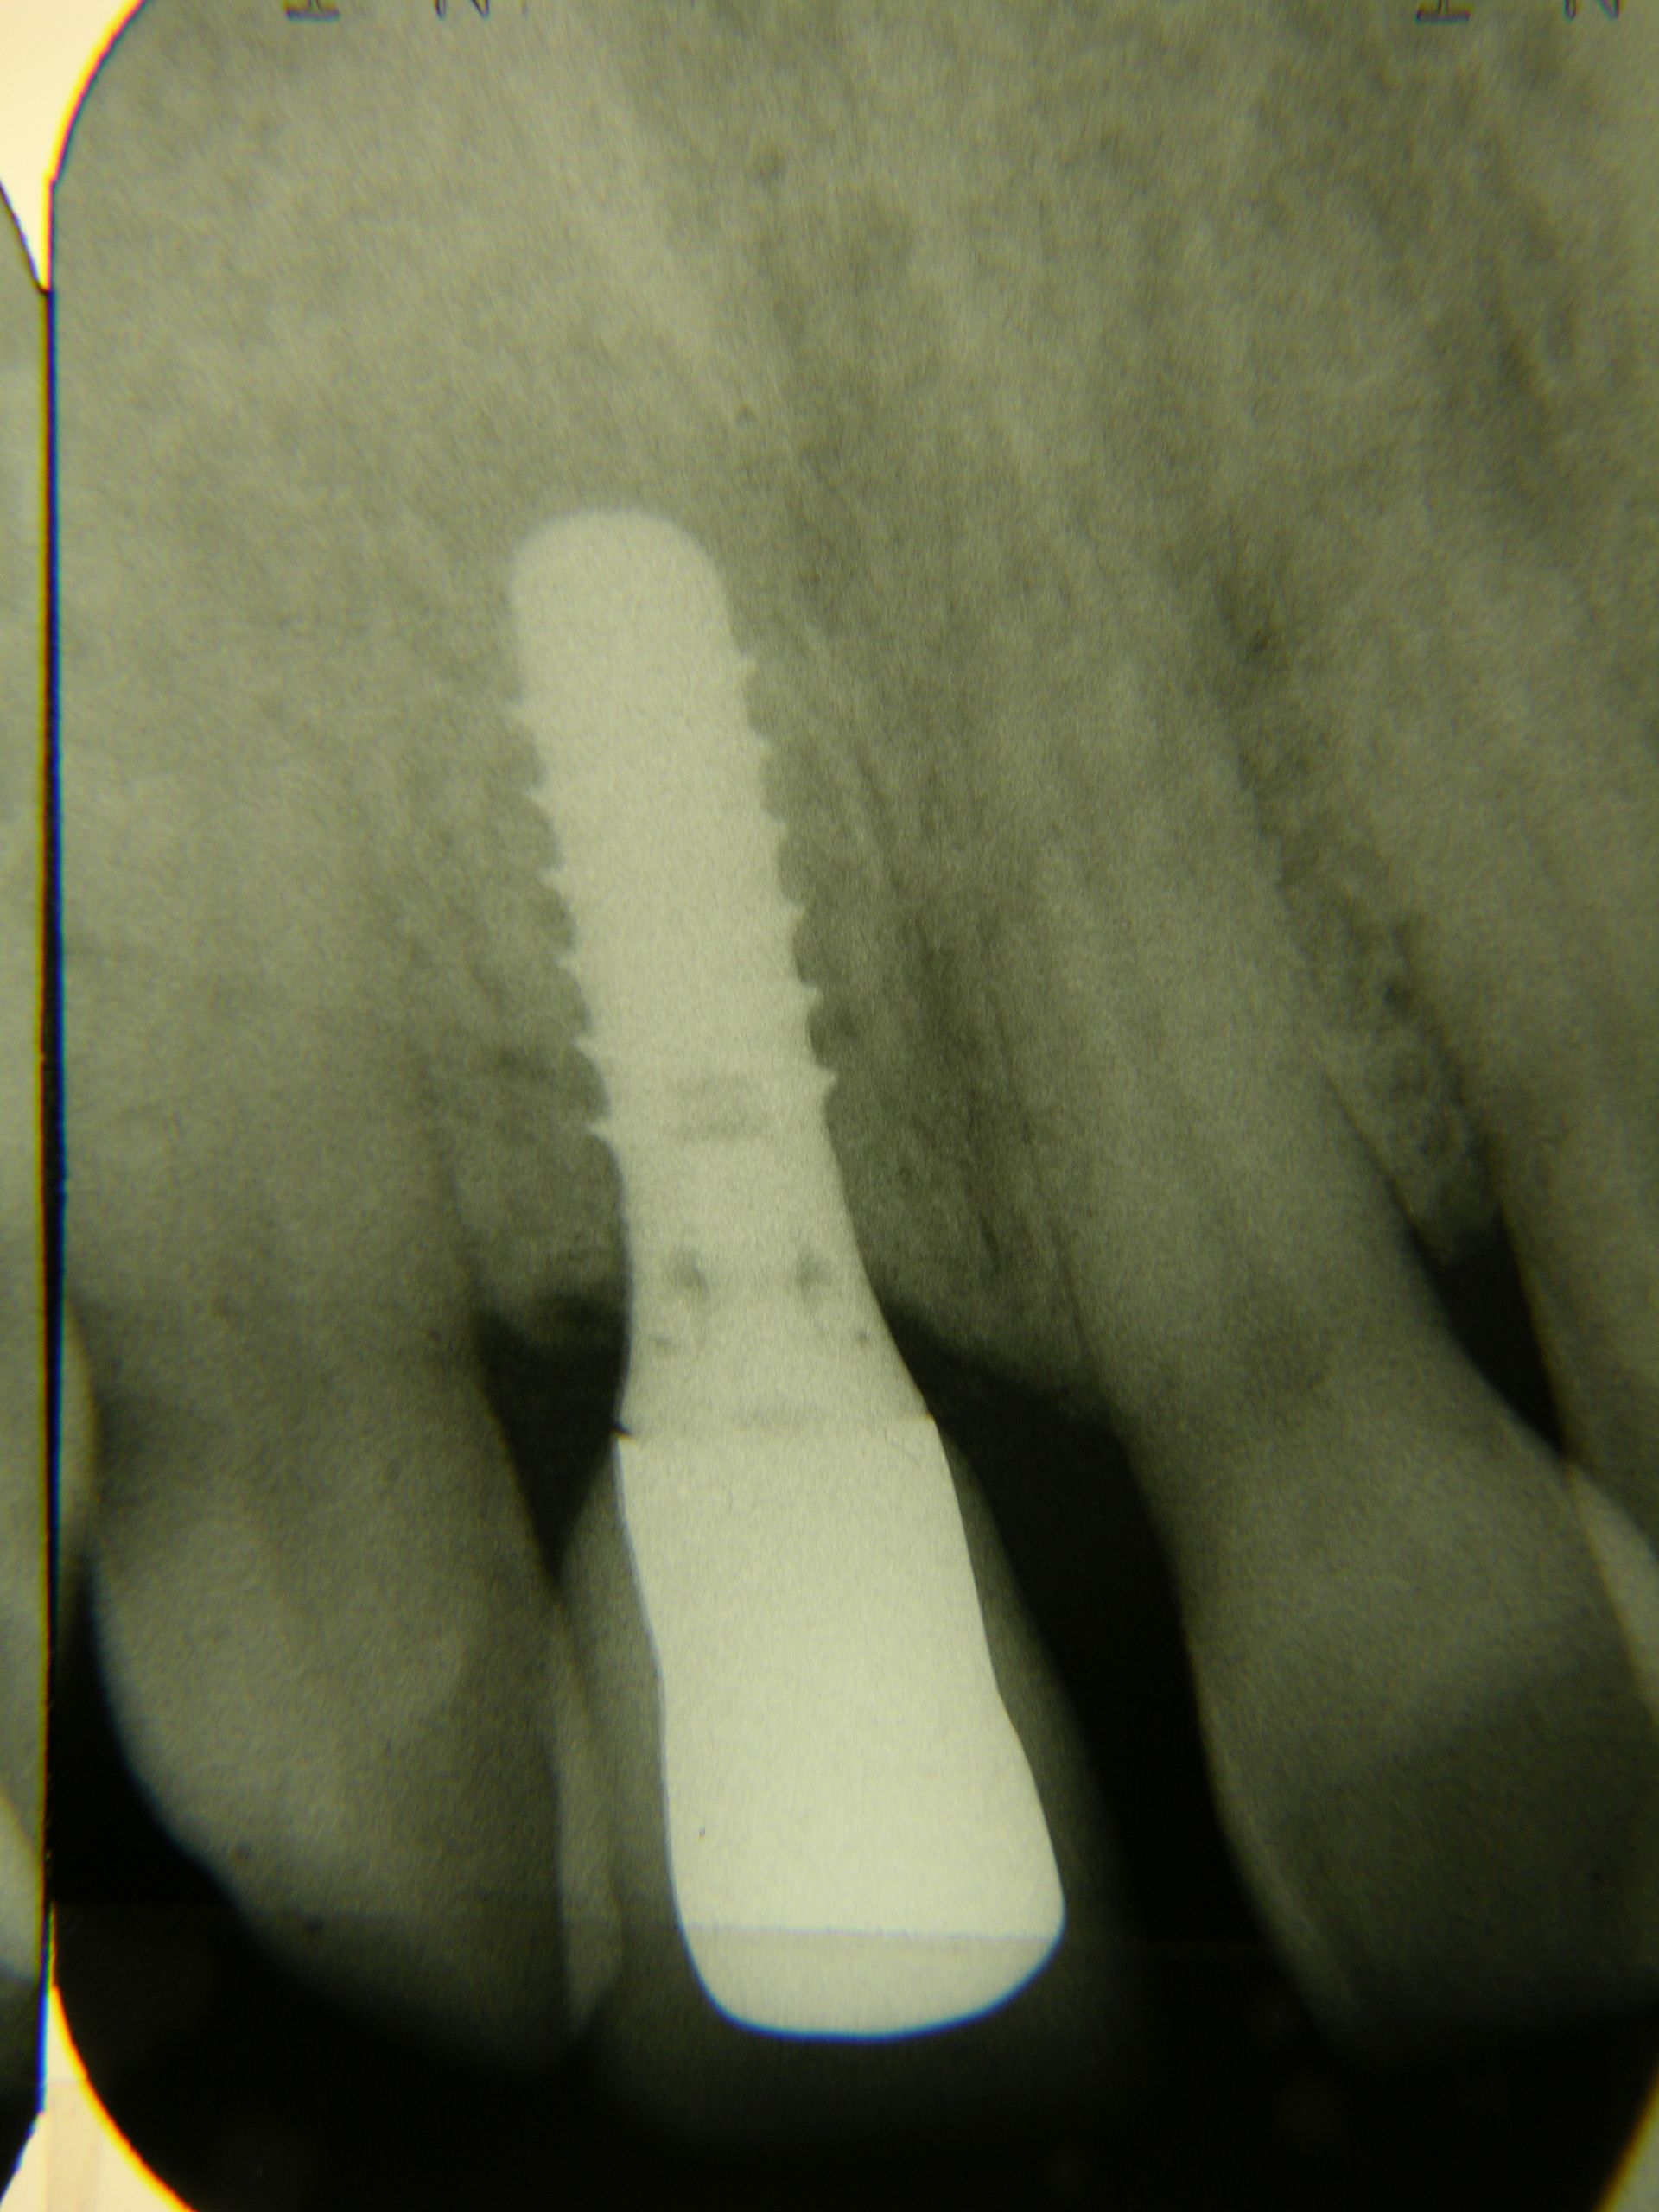

Beispiele von Versorgungen